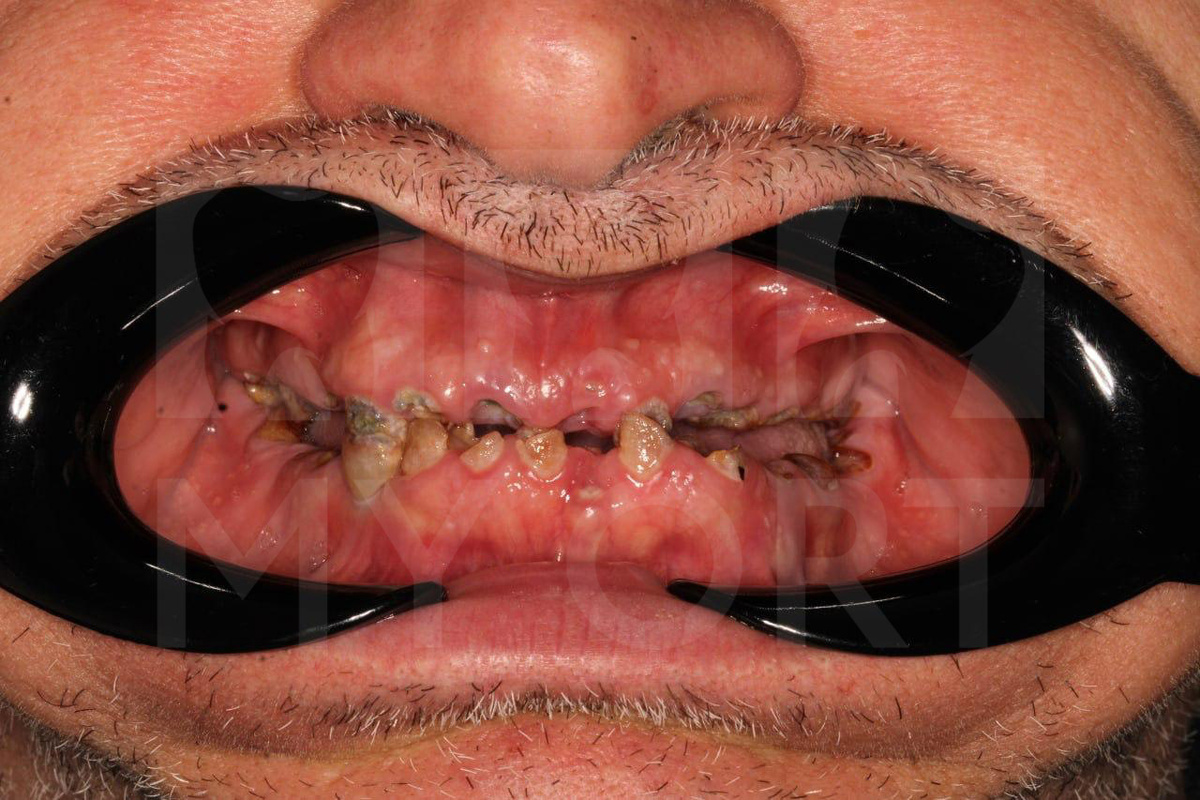

Жалобы пациента и диагностика

Пациент обратился ко мне на первичную консультацию с жалобами на невозможность нормально принимать пищу и отсутствие улыбки в течение многих лет. При осмотре полости рта было выявлено полное стирание зубов обеих челюстей, а также выраженное воспаление десен, что и вызывало сильный дискомфорт у пациента.

Рентгенологический анализ показал, что зубы не подлежат сохранению. Следующим шагом стало составление комплексного плана лечения.